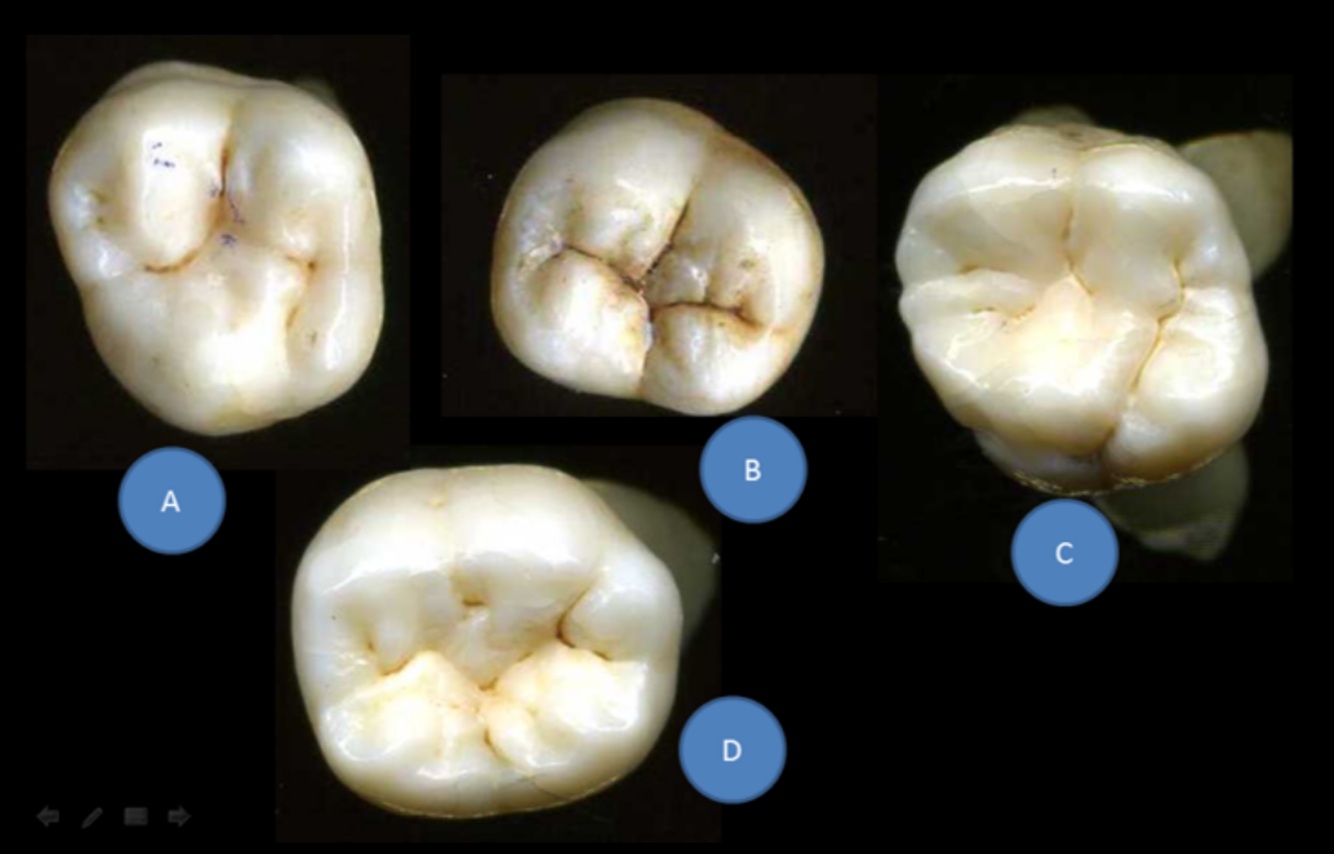

14

Q

One of these teeth has a small additional cusp on its biggest cusp in 60% of cases

A

C